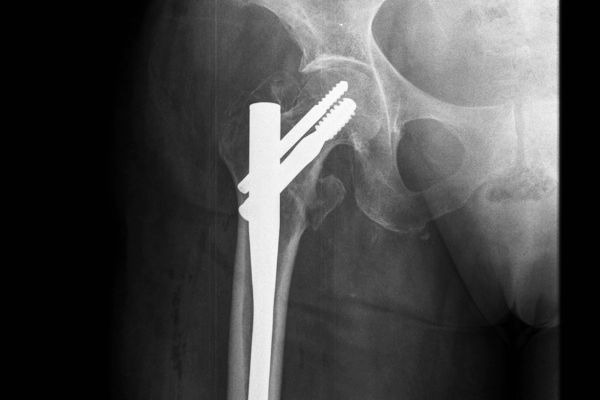

Gabinet ortopedyczny prowadzony przeze mnie specjalizuje się w leczeniu schorzeń i urazów kończyn górnych i dolnych. Zajmuję się leczeniem choroby zwyrodnieniowej stawu biodrowego i kolanowego, uszkodzeń wewnętrznych stawu kolanowego i barkowego, złamań w obrębie kończyn górnych i dolnych oraz urazów ścięgien i mięśni kończyn górnych i dolnych. Ponadto wykonuję diagnostykę USG narządu ruchu i badanie preluksacyjne (USG bioderek niemowląt). Leczę również neuropatie uciskowe kończyn (zespół kanału nadgarstka, rowka nerwu łokciowego, kanału Guyona) oraz uszkodzenia wewnętrzne stawów kończyn górnych i dolnych. Zapraszam do mojego gabinetu, gdzie dobiorę odpowiednie do schorzenia metody leczenia i zakwalifikuję do ewentualnego leczenia operacyjnego. W celu umówienia się na wizytę proszę o kontakt telefoniczny z rejestracją gabinetu ortopedycznego w Lesznie.